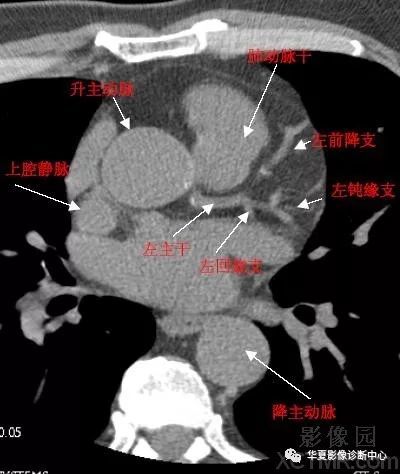

影像解剖心脏冠状动脉ct解剖中文详细标注图文

心脏ct横断面解剖图

心脏ct解剖

心脏ct解剖图